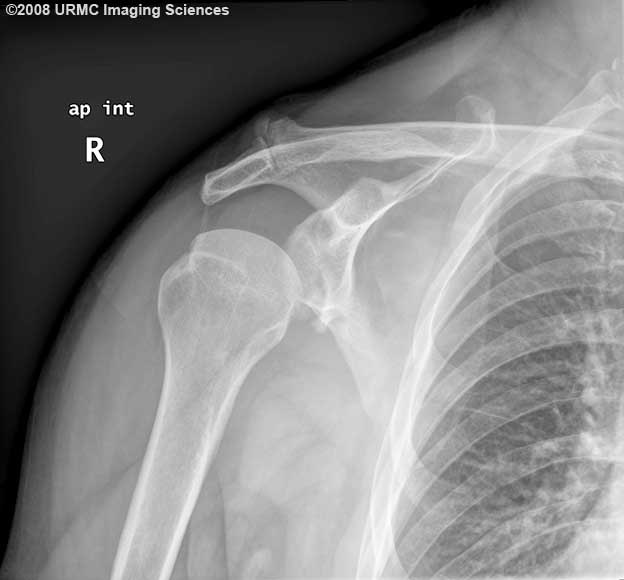

What 2 abnormalities are demonstrated on this radiograph?

AP internal rotation view of the shoulder shows a low-lying humerus suspicious for joint laxity and instability or pseudo-subluxation. Cortical depression of the posterolateral humerus is consistent with a Hill-Sachs deformity. Deformity of the inferior glenoid with a bony fragment is also present and suggests a glenoid fracture (bony Bankart injury).